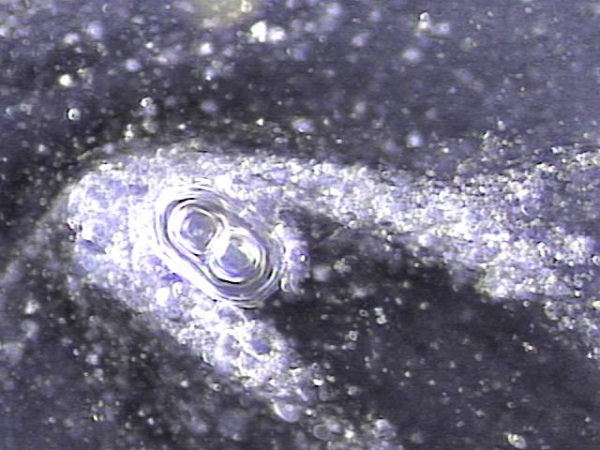

전립선과 사정관 그리고 사정관입구의 결석 치료중 사정관의 좁은 입구와 전립선관의 막혀 있는 입구로 커다란 결석이 배출시 압력으로 좁아져 있거나

막혀 있던 섬유화된 입구의 손상이 예상되는 현미경학적 사진입니다.

This is a microscopic image taken during the treatment of stones in the prostate, ejaculatory ducts, and the ejaculatory duct orifices.

It shows that large stones being expelled through the narrowed or obstructed fibrotic openings of the ejaculatory and prostatic ducts likely caused mechanical damage due to pressure during expulsion.